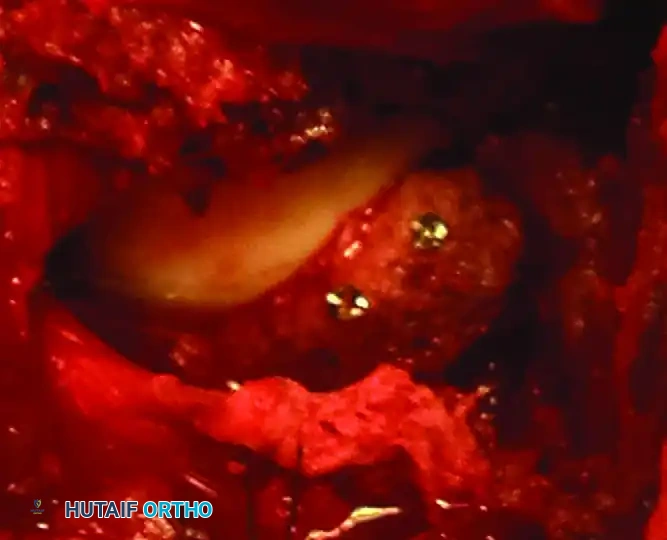

- Interval: The gluteus maximus is split in line with its fibers. The short external rotators (piriformis, obturator internus, gemelli) are tagged and released at their femoral insertions to expose the retroacetabular surface and the greater sciatic notch.

- Nerve Protection: The sciatic nerve must be identified and meticulously protected throughout the procedure. Keeping the hip extended and the knee flexed reduces tension on the nerve.